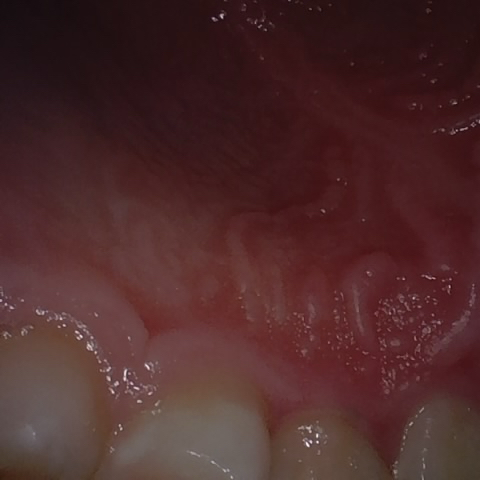

Annotated as "Good"